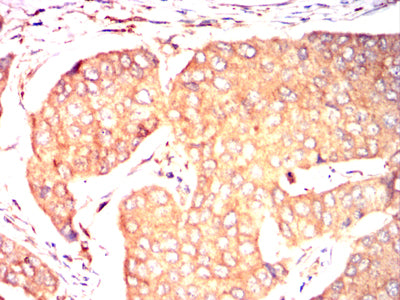

- Immunohistochemical analysis of paraffin-embedded human breast cancer tissues using NOTCH4 mouse mAb with DAB staining.